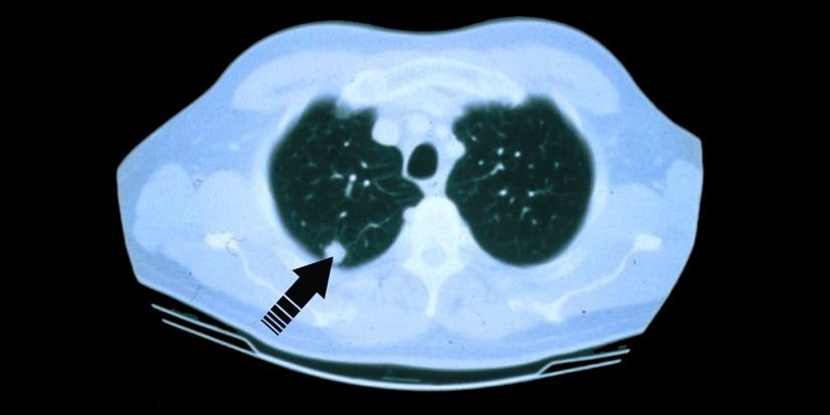

A low dose CT scan aids in finding cancer sooner and with early detection generally, more treatment options may be available.

Now more than ever, advanced screening can detect lung cancers earlier, so individuals can get better treatment outcomes. The screening utilizes a “low dose” CT scan to find any nodules especially in people who do not yet show any signs of lung cancer, but may be considered at high risk for the disease. Remember, the screening is a process, not a single test. An individual must adhere to the screening for early detection.